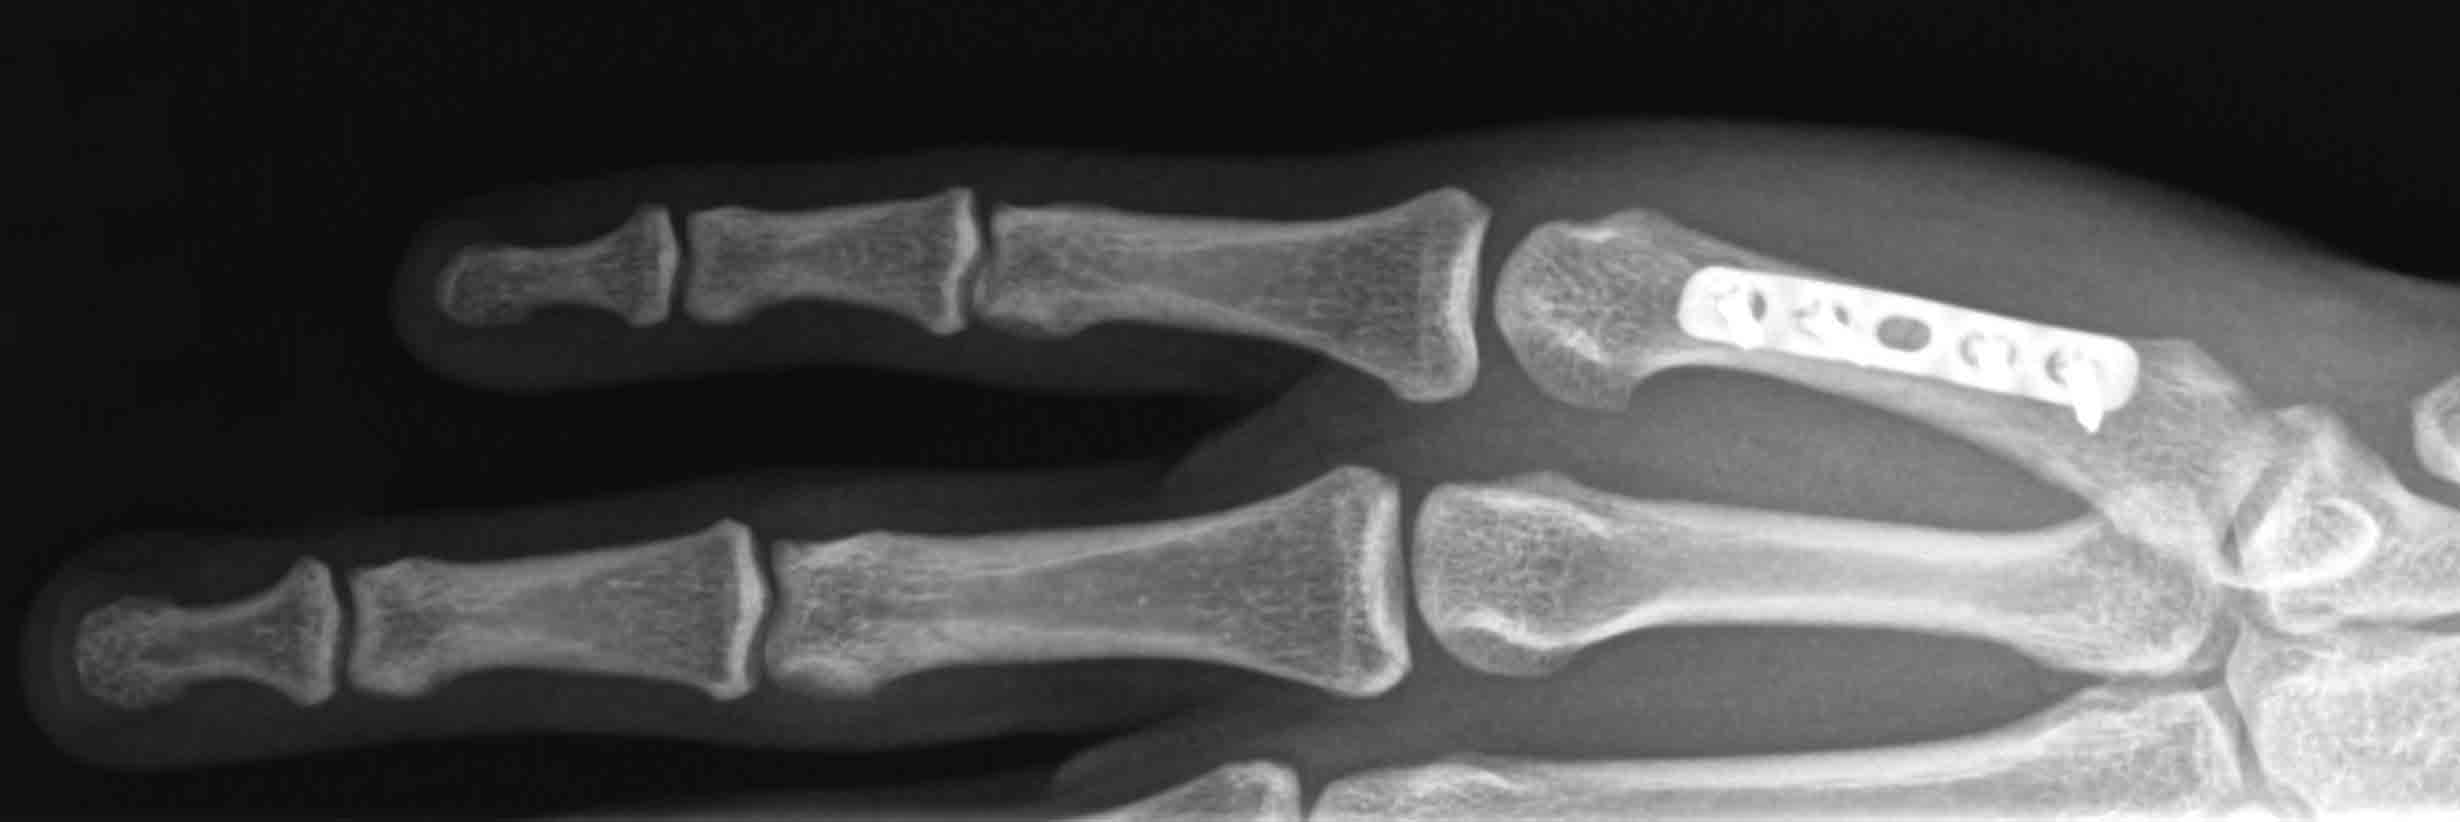

Sydney Hand Surgery » Hand Fractures

Hand Fractures OrthoInfo AAOS Hand Fracture Cast Types casts immobilize the joint above and the joint below the area that is to be kept straight and without motion. — jonathan grayzel, md, faaem. a hand fracture is a break in one of the bones in the hand. They’re either fiberglass or plaster. A broken hand can be caused by a fall, crush injury, twisting injury,. Hand Fracture Cast Types.